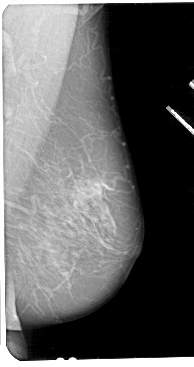

A_1112_1.LEFT_MLO

LEFT_MLO LINES 5116 PIXELS_PER_LINE 2731 BITS_PER_PIXEL 12 RESOLUTION 43.5 OVERLAY